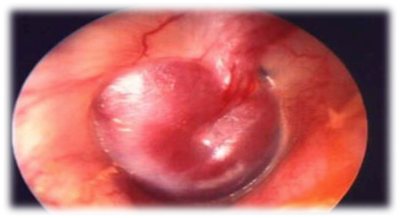

Paciente de 23 años de edad, sin antecedentes mórbidos de relevancia, consulta por cuadro de 4 días de evolución caracterizado por odinofagia intensa, tos seca, malestar general, rinorrea, Fiebre de 38,5ºC y otalgia derecha de intensidad moderada. A la otoscopía se evidencia la imagen adjunta.

Answer

• Otitis Externa Supurativa

• Otitis Externa Micotica

• Otitis Media Aguda

• Otitis interna